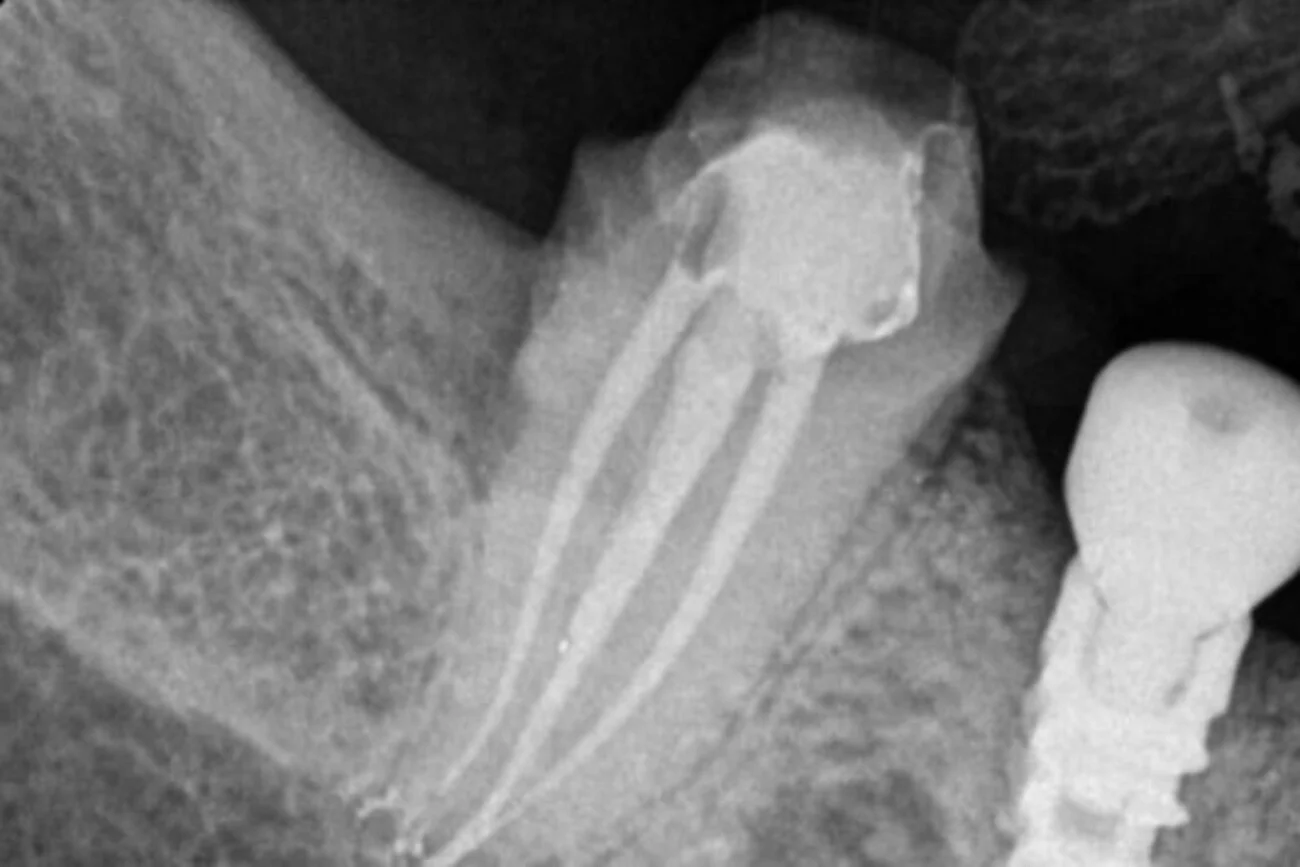

3D CBCT for Teeth Scanning:

Providing detailed 3D images of the teeth and surrounding structures. This aids in diagnosing complex root canal cases by offering a comprehensive view, enabling precise treatment planning.